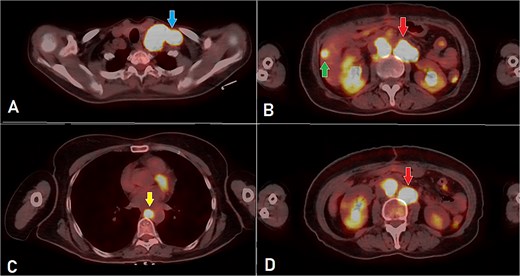

PET-CT scan (A) showing matted intensely hyper-metabolic left supraclavicular lymph nodes (arrow); (B) demonstrating intensely hyper-metabolic retroperitoneal lymph nodes (inferiorly pointing arrow) and a hyper-metabolic solitary hepatic lesion (superiorly pointing arrow); (C) demonstrating an intensely hyper metabolic mediastinal (para- oesophageal – station VIII) lymph node (arrow); and (D) revealing a few intensely hyper-metabolic retroperitoneal lymph nodes (arrow).